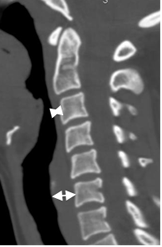

Igualmente tener en cuenta los espacios prevertebral y retrofaringeo, que se aumenta en casos de patología. El prevertebral se mide entre C1 y C4 y debe ser menor de 7 mm o el 30% del ancho del cuerpo vertebral. El retroesofágico entre C5 y C7 debe ser menor de 14 mm en los adultos y menor de 22 mm en los niños o igual al ancho del cuerpo vertebral. (10). (Fig 13).

Fig 13. Espacios normales.

TAC reconstrucción sagital. Espacio prevertebral sobre C3 y retroesofágico, a nivel de C6.